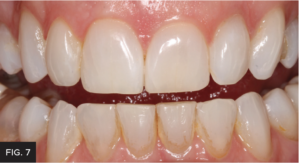

Post-operative full smile view after orthodontic treatment completed and shows the completed composite restoration.

Each layer of composite material and tints were cured with a high-power curing light. For the final curing, glycerin was placed on the restoration’s surface to remove the oxygen inhibited layer; this hardened the surface and made it easier to achieve a beautiful polish. (FIG 7)

Photographs were taken to evaluate aesthetic outcome. The patient was shown her new restoration and was pleased with the results. The patient returned a few weeks later for a final post-op check. The tissue healed well after removal of the attachments. Proper canine function was confirmed and lateral disclusion of the lateral was obtained which is ideal with a Class IV restoration on such a small sized tooth.12 The final pictures2 and post-op x-rays were taken. (FIG 8 & 9)